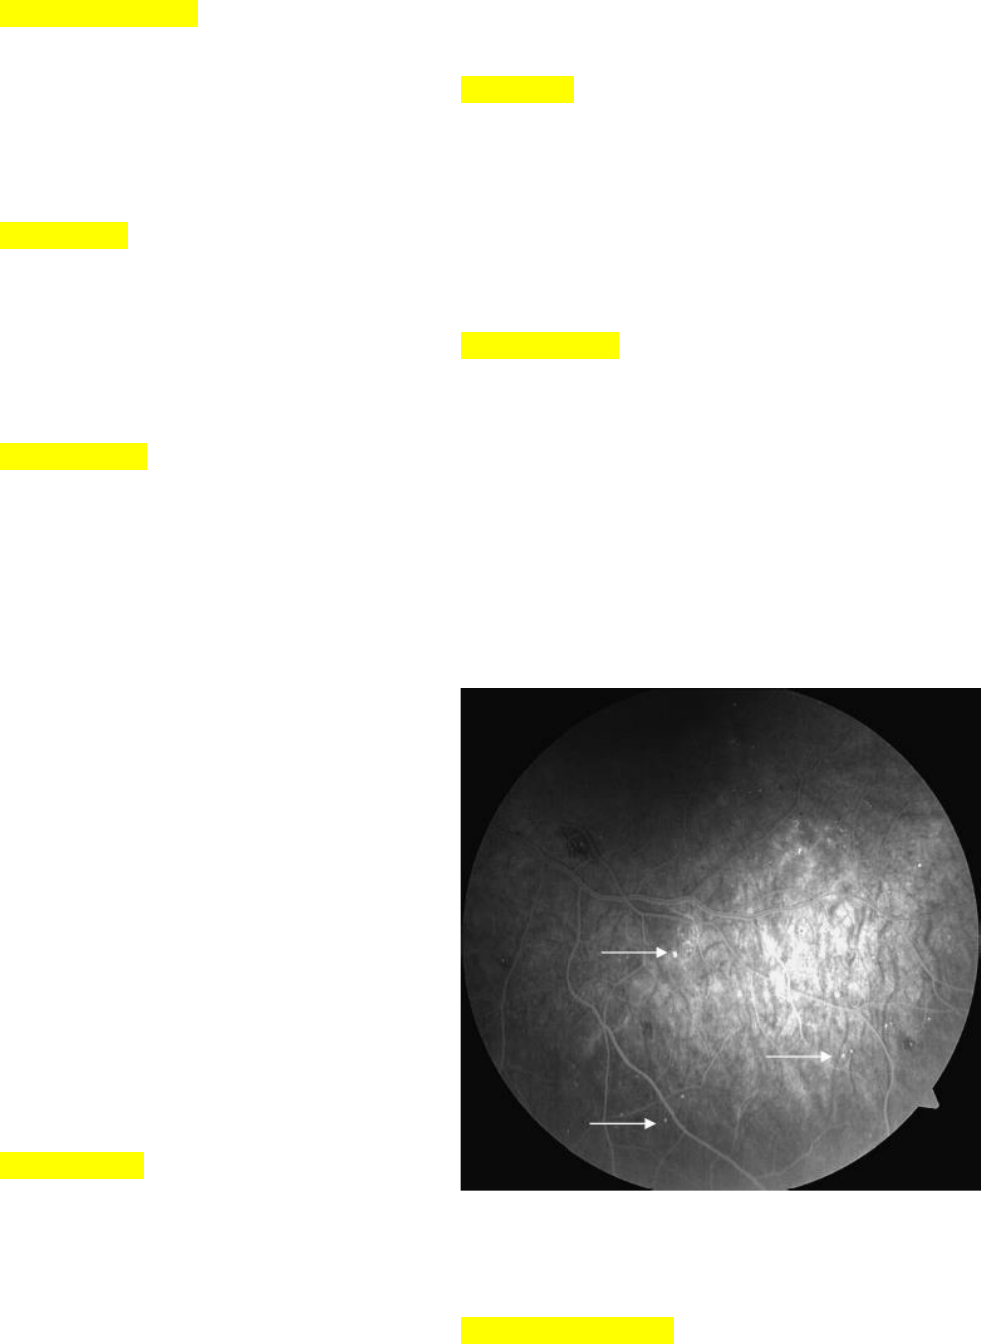

Figura 1 Angiofluoresceinografia em paciente com

retinopatia diabética não proliferativa leve com

pontos de hiperfluorescência referente a

microaneurismas

• Primeiro sinal aparente (após perda

dos pericitos)

• Herniações saculares nas paredes

dos vasos retinianos

• Localizados predominantemente na

camada plexiforme interna

• Pontos avermelhados nas camadas

superficiais retinianas

• Ruptura provoca hemorragia

intrarretiniana